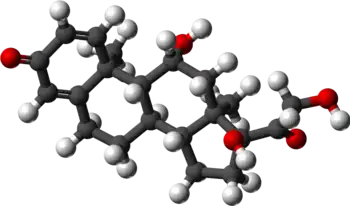

| Various pharmaceutical tuberculosis treatments and their actions | |